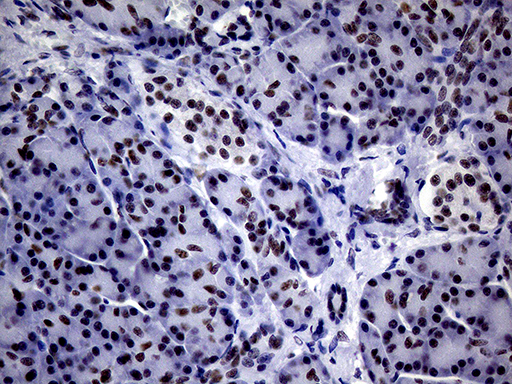

Immunohistochemical staining of paraffin-embedded Adenocarcinoma of Human breast tissue tissue using anti-BRCA1 mouse monoclonal antibody. (Heat-induced epitope retrieval by 1mM EDTA in 10mM Tris buffer (pH8.0) at 120°C for 3min, M00005-1) (1:200)